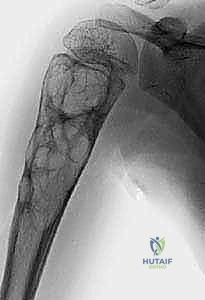

في الـ ABC، تظهر الآفة غير مركزية، متمددة، وتدفع قشرة العظم للخارج لتصبح رقيقة جداً مثل "قشرة البيضة".

تُظهر هذه الأشعة السينية كيس عظم متمدد (ABC). لاحظ التوسع الكبير في العظم وترقق القشرة العظمية مقارنة بالكيس أحادي الغرفة.